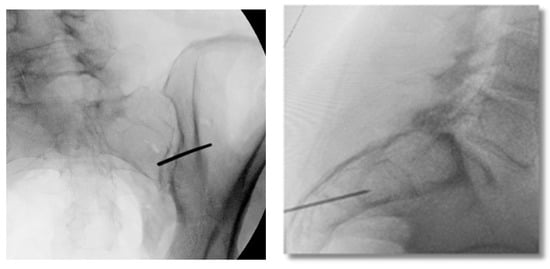

3.3.9. Final Implant Placement